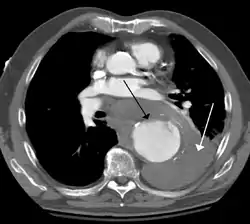

Thoracic aortic aneurysm (TAA) is an aortic aneurysm that occurs above the diaphragm.[4] Initially there are generally no symptoms.[2] Occasionally chest pain, shortness of breath, superior vena cava syndrome, or hoarseness may occur.[2] Complications may include aortic dissection, aortic regurgitation, or aortic rupture.[2]

Diagnosis

Thoracic aortic aneurysm is defined as a cross-sectional diameter exceeding the following cutoff:

• 4.5 cm in the United States[10]

• 4.0 cm in South Korea[11]

A diameter of 3.5 cm is generally considered dilated.[10] However, average values vary with age and size of the reference population, as well as different segments of the aorta.